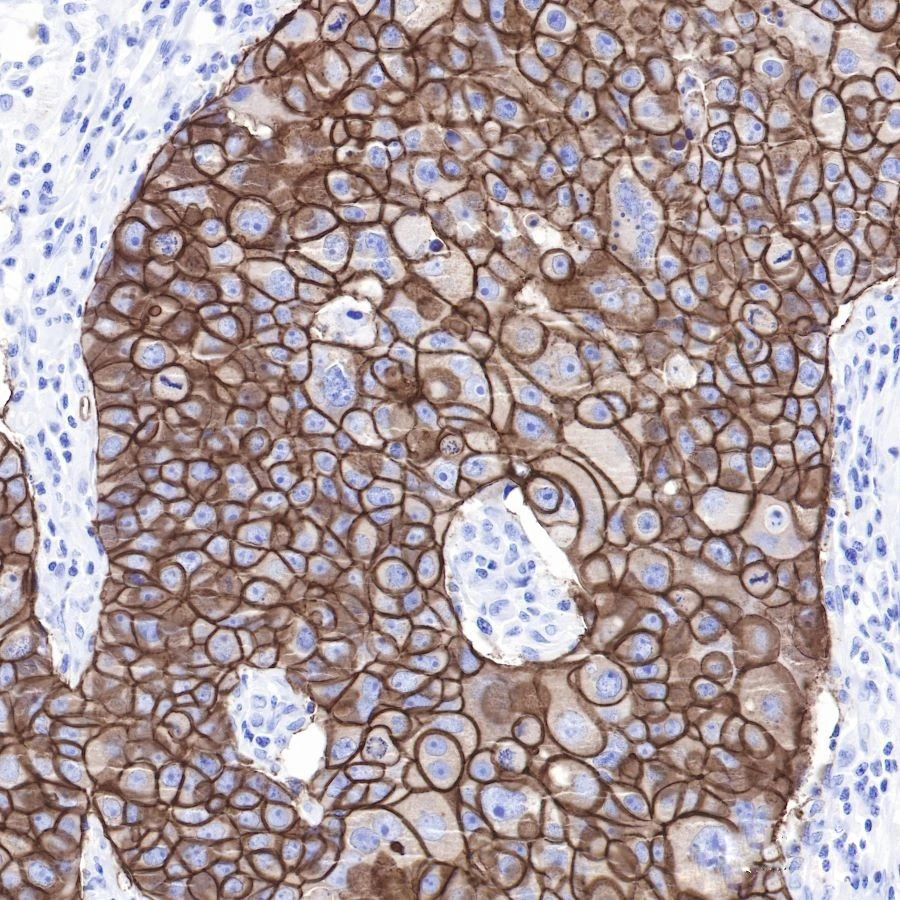

免疫组织化学(IHC)技术是一种通过标记特异性抗体来检测抗原的细胞化学方法。在乳腺癌检测中,IHC技术被广泛应用于HER2、ER、PR等乳腺癌相关抗原的检测。其中,HER2蛋白过表达的检测对于指导靶向治疗具有重要意义。斯达特的乳腺癌相关抗体,正是基于IHC技术而研发,为精准诊断和治疗乳腺癌提供了可靠的工具。

1、ErbB2

HER2 (ErbB2) 是人类表皮生长因子受体(HER/EGFR/ERBB)家族的一个成员。但与ERBB家族的其他成员相反,HER2并不直接结合配体。例如在癌症中,HER2的激活来自于与另一个ERBB成员的异源二聚体或当HER2浓度高时的同源二聚体。HER2基因的扩增或过度表达,从而促进肿瘤的生长和进展。HER2阳性乳腺癌患者通常具有更高的肿瘤增殖活性、更强的侵袭能力和更短的生存期。近年来,该蛋白已成为约30%的乳腺癌患者的重要生物标志物和治疗靶点。